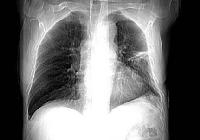

PA chest radiograph performed 5 months after mantle

radiation therapy of the mediastinum for treatment of Hodgkin's disease, shows typical

consolidation and air bronchograms strictly confined to the areas corresponding to the

radiation field. |

Chest Xray Findings: Chest radiographic

findings vary from normal or subtle hazy ground glass density to marked patchy or

homogenous consolidation. Air bronchograms are commonly present and volume loss of the

affected portion of the lung may be observed. There is usually a sharp boundary crossing

the normal anatomic structures without segmental or lobar distribution. Rarely, an entire

lung or both lungs are involved (adult respiratory distress syndrome [ARDS]).False